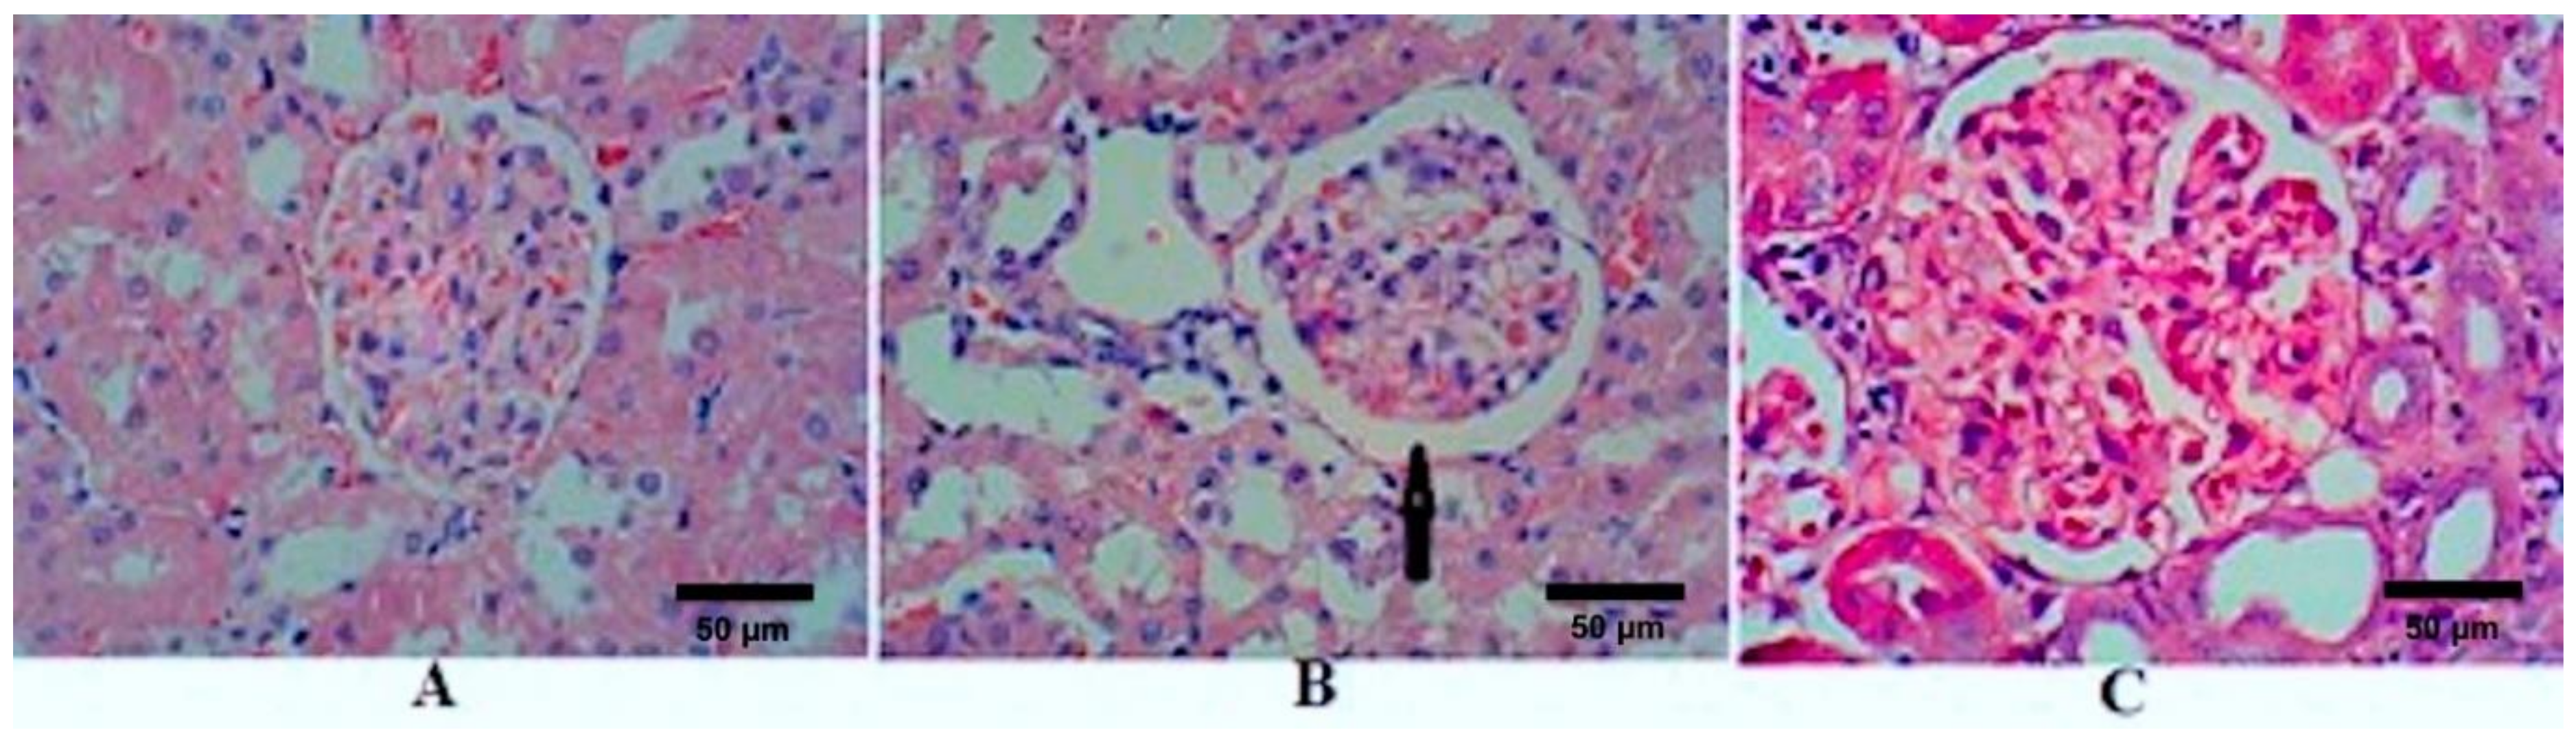

Kidney sections stained with HE of the control rats (group I) showed normal GM (Figure 1A). After 4 weeks of STZ treatment, sections showed an increase in the diameter of RC, GM, and BS in the untreated diabetic rats (group II); however, GM did not achieve a statistical difference (Figure 1B and Table 2). There were reversible changes after the treatment with TQ (group III), which showed a significant reduction in RC, GM, and BS (Figure 1C). The diameters of RC, GM, and BS of TQ-treated rats decreased and became comparable with the control group (Table 2). Figure 2 and Table 2 show the effects of STZ and TQ on tubulointerstitial morphology (upper image) and arteriolosclerosis (lower images). Control group shows normal tubulointerstitial morphology and grade 0 arteriolosclerosis (Figure 1A). The inflammatory cell infiltration and hyaline droplets in untreated (group II) and TQ-treated (group III) diabetic rats are shown in Figure 1B and C, respectively. The vertical black arrow indicates hyaline droplets, inflammatory cells are enclosed in a black circle, and arterioles are indicated by horizontal black arrows. Arteriolosclerosis was observed in the untreated diabetic group in most of the examined fields, where wall diameter exceeded that of the lumen in nearly all sclerotic arterioles. However, the degree of sclerosis was markedly reduced in TQ-treated diabetic rats. The renal tubules were dilated and hypertrophied in the untreated diabetic group in comparison to the TQ-treated diabetic group (Table 2, Figure 1 and Figure 2).

Figure 1.

Effects of streptozotocin (STZ) and TQ on glomerular morphology. (A) Control group (Group I), (B) untreated diabetic group (Group II), and (C) TQ-treated diabetic group (Group III). The black arrow indicates an increase in Bowman’s space. H&E staining, magnification = 400 X.

The present study sought to elucidate the short-term effects of TQ as a safe natural product for treatment and controlling oxidative stress, glycaemic control, lipid profile, and renal functions in diabetic rats. The present study revealed several findings. First, we demonstrated that inducing DM in Sprague-Dawley rats significantly disturbs the normal redox state, as was indicated by altered levels of lipid peroxidase, NO, and TAC in untreated diabetic rats relative to control rats. Similar to the findings of Siboto et al. [41] and Sassy-Prigent et al. [42], histopathology in the present study revealed that injecting rats with STZ resulted in glomerular hypertrophy, which could be largely attributed to mesangial expansion and the thickening of the glomerular basement membrane.

Another important finding is that treating diabetic rates with TQ successfully improved glycaemic control and attenuated oxidative stress. Interestingly, we observed that the levels of lipid peroxidase, NO, and TAC were similar or better in diabetic rats treated with TQ compared to control rats, indicating that TQ exerts a positive effect on oxidative stress. Additionally, treatment with TQ decreased the diameter of the RC in comparison to that of untreated diabetic rats, while the diameter of BS in diabetic rats treated with TQ decreased even beyond that of control rats. This can be attributed to the capsular thinning and glomerulus preservation observed when comparing the glomerulus diameters in treated and untreated diabetic groups. Ozdemir et al. [43] reported a direct relationship between an increase in the area of BS and blood glucose levels in STZ-induced diabetic nephropathy. The present study demonstrates that treatment with TQ reduces arteriosclerotic changes in the kidney sections taken from treated diabetic rats. Arteriolosclerosis is widely reported in cases of diabetic nephropathy and represents one of the underlying pathophysiological mechanisms of this disease, in addition to oxidative stress and associated inflammation [44].